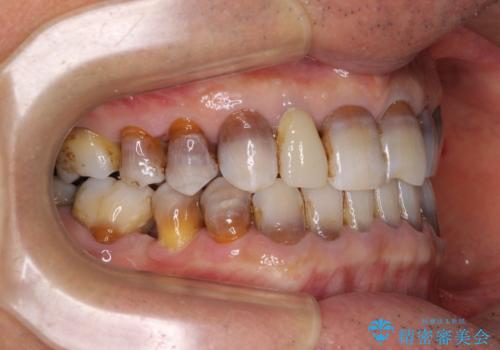

- 前歯のクロスバイトを気にして来院された患者様です。

骨格的に下顎が前方位ではありますが、歯並びが改善されれば正常咬合となることが分かったため、インビザラインを用いて咬み合わせを改善していくこととしました。